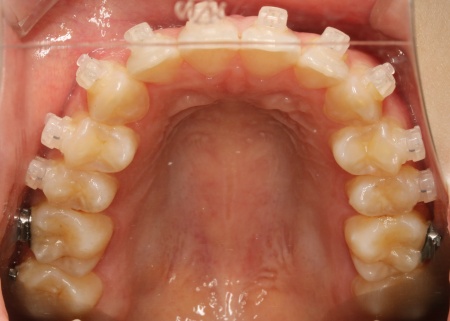

治療中

| 行った治療内容 | 患者様は「できるだけ目立たない治療方法で、なるべく早く終わらせたい」と希望されていたため、ハイブリッド矯正を提案し、同意いただきました。 ハイブリッド矯正とは、ワイヤー矯正とマウスピース矯正の両方を行う方法です。先にワイヤー矯正で歯を大きく移動させたあと、マウスピース矯正で仕上げることで、治療期間の短縮が望めます。 ただ2種類の矯正装置を使用するため、単独での矯正治療よりも費用が高くなる点がデメリットです。 ・ワイヤー矯正 歯の表面にブラケットと呼ばれるボタン状の装置を接着し、そこにワイヤーを通して歯を移動させる方法です。 患者様は目立たない治療方法を望まれていたため、ブラケットには白く目立ちにくい「セラミックブラケット」を選択しました。 ・マウスピース矯正 患者様専用のマウスピース(アライナー)を複数個作製して、定期的にご自身で交換しながら歯を移動させる方法です。 今回は、アライナーの枚数に制限がないプランである「インビザライン・コンプリヘンシブ」を選択しました。 まずは歯の表面にセラミックブラケットを装着し、ワイヤー矯正で歯を全体的に移動させます。 歯並びがある程度正しい位置に並んだら、マウスピース矯正で微調整を行いました。 歯の移動が完了したあとは定期的に経過を確認しながら、後戻りを防ぐためのリテーナー(保定装置)を継続して使用いただき、治療を終了しました。 |